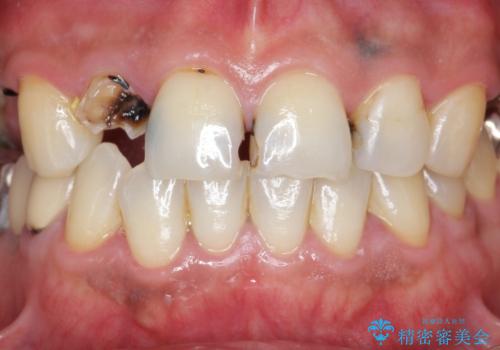

「 放置した虫歯 」 前歯セラミック治療

- 前歯の虫歯に気付きながらも放置し、一念発起し治療を希望され来院されました。

虫歯のマイクロスコープによる丁寧な除去、根管治療、深い虫歯に対する挺出(エクストリュージョン)および歯周外科を行ったのち精度の高いセラミッククラウン製作治療を計画します。

虫歯の放置により、根管治療や深い虫歯に対する処置が必要になりましたが丁寧に一つづつ処置を行ったことで抜歯をすることなく歯を残すことができました。